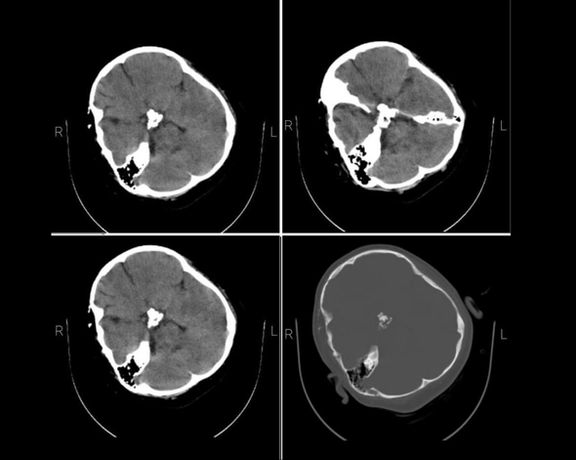

The skull CT scan of Mahsa Amini, the Iranian woman who died in religious police custody, shows bone fracture, hemorrhage and brain edema, Iran International has learned.

The medical documents and dozens of exclusive images sent to Iran International by a hacktivist group vividly show a skull fracture on the right side of her head caused by a severe trauma to the skull, which corroborate earlier accounts by her family and doctors about her being hit several times on the head, proving that the Iranian police's claim that she suffered a heart attack was untrue.

A source from the hospital where she died told Iran International on Saturday that her brain tissue was crushed after "multiple blows" to the head, adding that Amini was taken to Kasra Hospital in capital Tehran while she was not responsive and brain dead.

This source emphasized that Mahsa's condition "was such that she could not be saved nor was surgery possible because her brain tissue was seriously damaged and it was clear that the patient was not injured by a single punch and must have received many blows to her head."